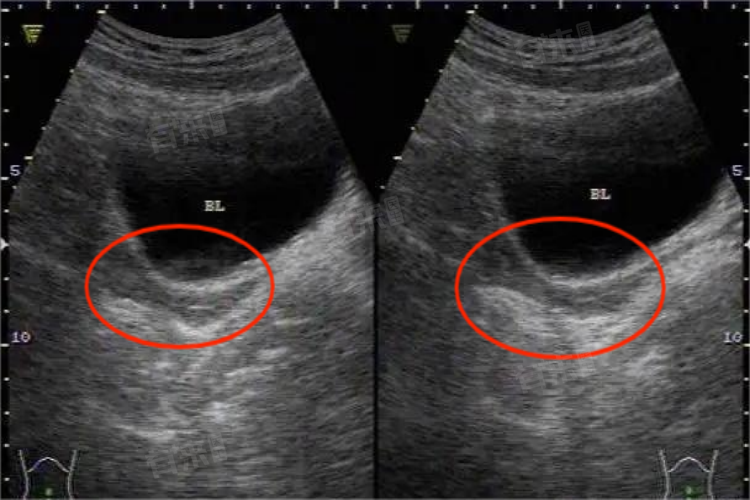

幼稚子宫通常不适合做试管怀孕。从医学解剖结构来看,幼稚子宫是因先天性发育不良,子宫体积显著小于正常,常呈细长形或极度前屈、后屈状态。这种结构异常使得子宫腔空间狭小,无法为移植后的胚胎提供充足的生长发育空间,即便进行试管胚胎移植,也难以满足胎儿正常发育需求。

- 在生理功能方面,幼稚子宫的内膜发育往往不完善。正常受孕及妊娠过程中,子宫内膜需要在激素作用下发生周期性变化,为胚胎着床提供适宜环境。而幼稚子宫的内膜过薄,腺体和血管分布稀疏,无法形成良好的容受性,胚胎难以成功着床,即使着床也容易因缺乏营养支持而导致流产。